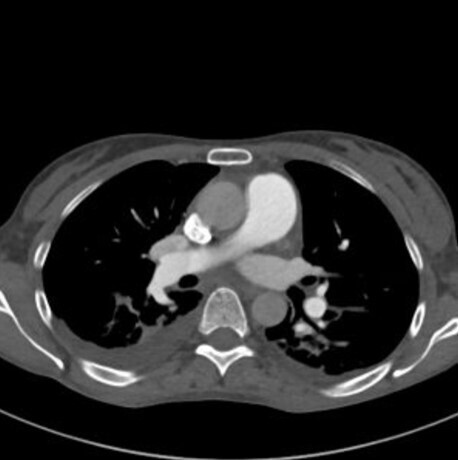

Lors de cette surveillance échographique, une image nodulaire du dôme hépatique apparaît. Le scanner ci-dessous est réalisé pour caractériser cette lésion.

Question 8 - Les caractéristiques sémiologiques de cette lésion sont :

La lésion est hypodense sans injection, mais de densité plus élevée que la graisse sous-cutanée qui apparait presque noire ici (NB : le CHC graisseux est une entité qui existe mais rare).

Le temps artériel se reconnait grâce à la densité importante des artères (par exemple l’aorte).

On parle d’hyperdensité en scanner et d’intensité en IRM.

Un envahissement tumoral vasculaire se manifesterait sous la forme d’une plage infiltrante hypervasculaire au temps artériel au sein de la veine.

Lésion nodulaire typique de carcinome hépatocellulaire (CHC) en scanner : nodule bien délimité hypodense sans injection, hypervasculaire au temps artériel (« wash-in »), présentant un lavage au temps portal et tardif (« wash-out »), et une capsule (dont la définition est la présence d’une couronne se rehaussant au temps tardif).

Un scanner réalisé pour caractérisation d’une lésion hépatique doit comprendre une phase sans injection, une phase artérielle, une portale et une tardive à 3 minutes. Un scanner thoracique pourra également être réalisé dans le bilan d’extension du CHC.

L’imagerie est donc évocatrice de carcinome hépatocellulaire (CHC).